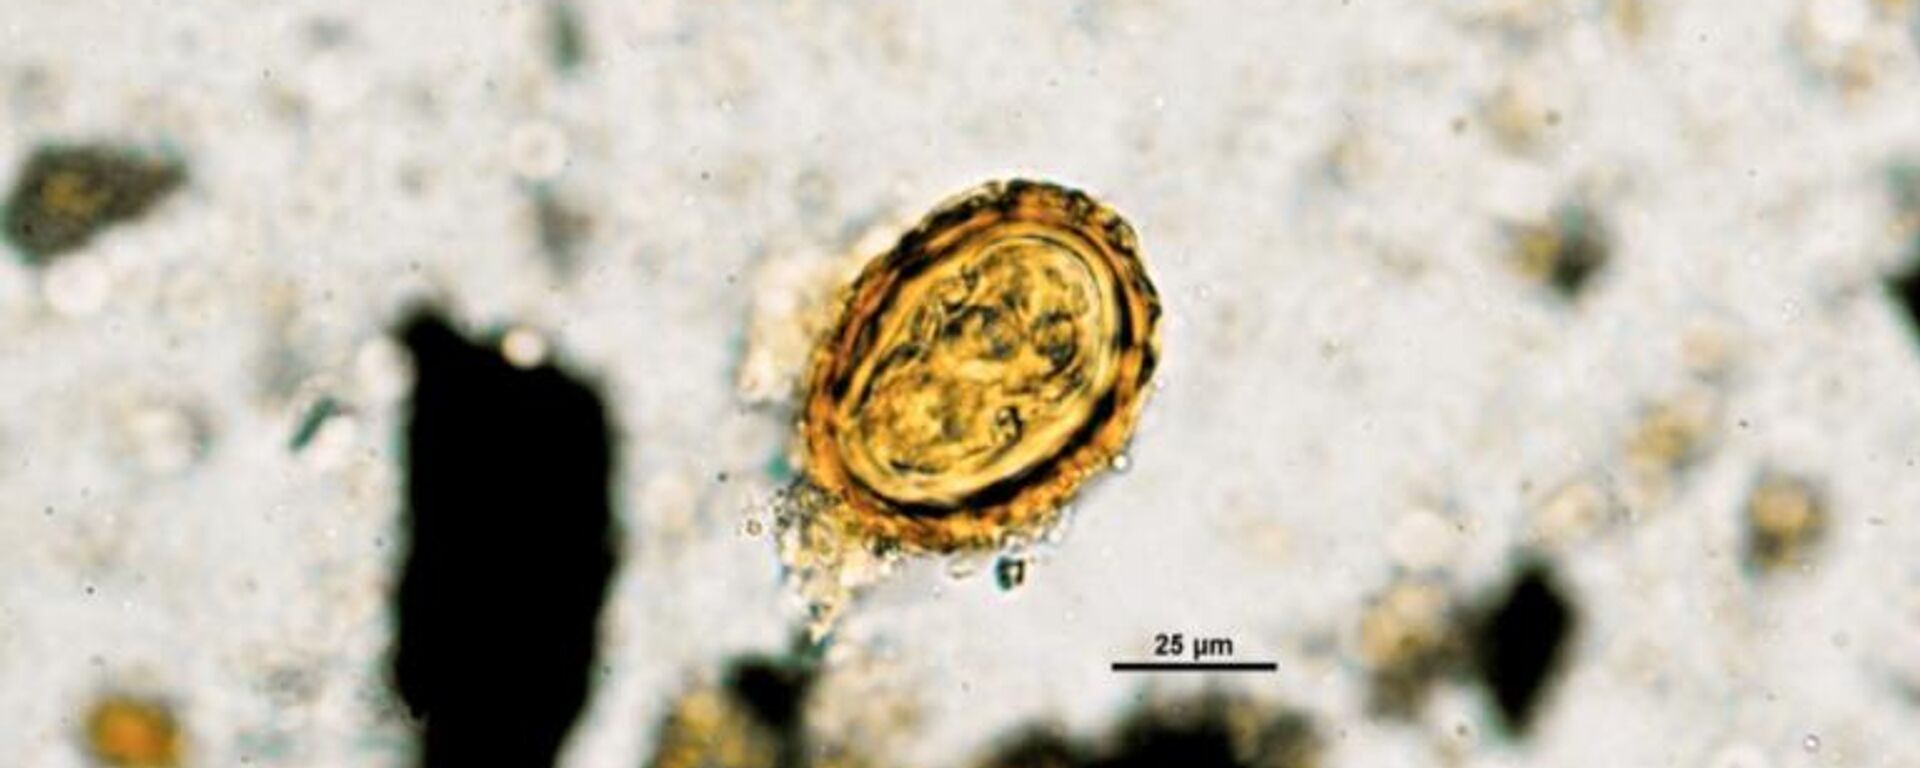

https://noticiaslatam.lat/20230829/hallan-huevos-de-helmintos-en-las-paleoheces-de-los-antiguos-mineros-de-sal--foto--1143139080.html